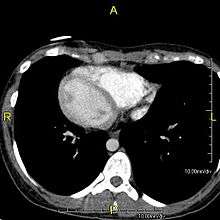

| Normal cilia (A) and cilia representative of Kartagener's syndrome (B). | |